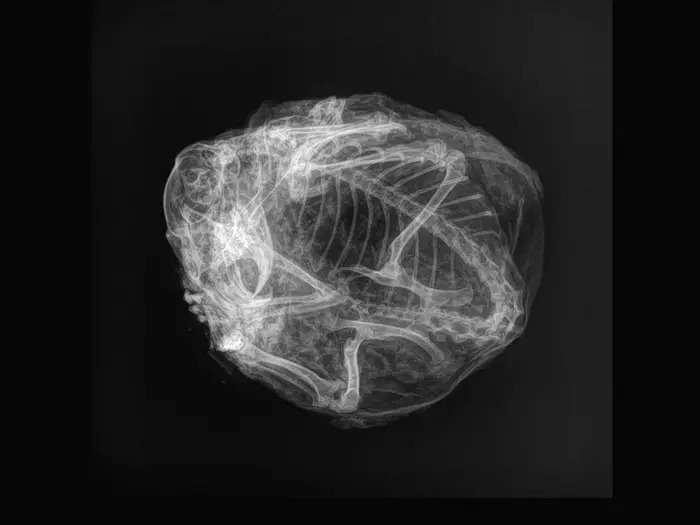

Xác ướp quái thú này khi chụp X-quang khiến các nhà khoa học vô cùng phấn khích.

Ban đầu, các nhà khoa học không thể nhận biết hình dạng của xác ướp. Bề ngoài của nó phủ một lớp lông màu nâu vàng, có kích thước tương đương quả bưởi, với đôi tay có vuốt nhọn.

Sau khi chụp X-quang, họ nhận ra đó là một con sóc đất Bắc Cực cổ đại thuộc chi Urocitellus parryii. Điều đặc biệt là nó giống với sóc đất Bắc Cực hiện đại. Sóc này sống trên địa hình Bắc Cực ở cả hai bên eo biển Bering.